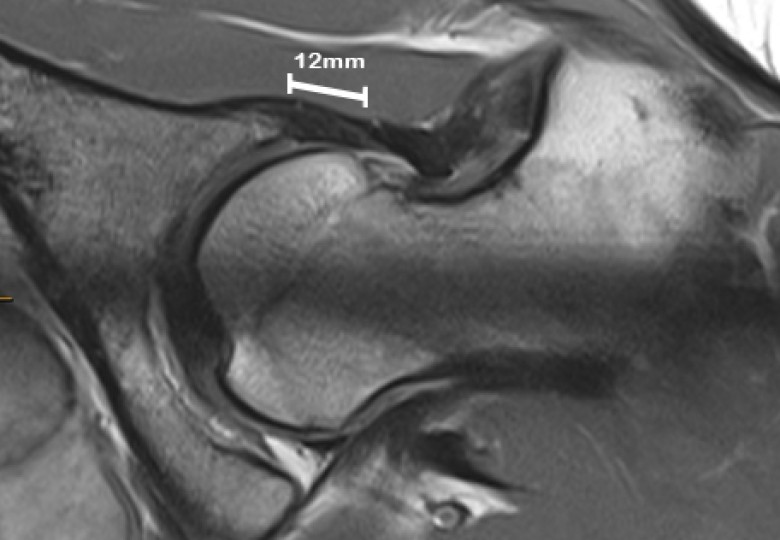

- Increased acetabular anteversion (a measure of the angle of the hip socket) and decreased lateral centre edge angle (LCEA, a measure of hip socket coverage) were associated with microinstability.